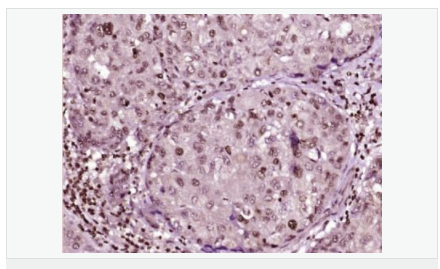

| 英文名稱(chēng) | phospho-HSP70 (Tyr611) |

| 中文名稱(chēng) | 磷酸化熱休克蛋白-70抗體 |

| 交叉反應 | Human, Mouse, Rat, (predicted: Dog, Pig, Rabbit, Guinea Pig, ) |

| 產(chǎn)品應用 | ELISA=1:5000-10000 IHC-P=1:100-500 IHC-F=1:100-500 Flow-Cyt=1μg/Test ICC=1:100 IF=1:100-500 (石蠟切片需做抗原修復) not yet tested in other applications. optimal dilutions/concentrations should be determined by the end user. |

| 產(chǎn)品介紹 | This intronless gene encodes a 70kDa heat shock protein which is a member of the heat shock protein 70 family. In conjuction with other heat shock proteins, this protein stabilizes existing proteins against aggregation and mediates the folding of newly translated proteins in the cytosol and in organelles. It is also involved in the ubiquitin-proteasome pathway through interaction with the AU-rich element RNA-binding protein 1. The gene is located in the major histocompatibility complex class III region, in a cluster with two closely related genes which encode similar proteins. [provided by RefSeq, Jul 2008]. Function: In cooperation with other chaperones, Hsp70s stabilize preexistent proteins against aggregation and mediate the folding of newly translated polypeptides in the cytosol as well as within organelles. These chaperones participate in all these processes through their ability to recognize nonnative conformations of other proteins. They bind extended peptide segments with a net hydrophobic character exposed by polypeptides during translation and membrane translocation, or following stress-induced damage. In case of rotavirus A infection, serves as a post-attachment receptor for the virus to facilitate entry into the cell. Subunit: Component of the CatSper complex. Identified in a mRNP granule complex, at least composed of ACTB, ACTN4, DHX9, ERG, HNRNPA1, HNRNPA2B1, HNRNPAB, HNRNPD, HNRNPL, HNRNPR, HNRNPU, HSPA1, HSPA8, IGF2BP1, ILF2, ILF3, NCBP1, NCL, PABPC1, PABPC4, PABPN1, RPLP0, RPS3, RPS3A, RPS4X, RPS8, RPS9, SYNCRIP, TROVE2, YBX1 and untranslated mRNAs. Interacts with TSC2. Interacts with IRAK1BP1. Interacts with TERT; the interaction occurs in the absence of the RNA component, TERC, and dissociates once the TERT complex has formed. Interacts with DNAJC7. Interacts with CHCHD3. Subcellular Location: Cytoplasm. Note=Localized in cytoplasmic mRNP granules containing untranslated mRNAs. Tissue Specificity: HSPA1B is testis-specific. Similarity: Belongs to the heat shock protein 70 family. SWISS: P0DMV8 Gene ID: 3303 Database links: Entrez Gene: 3303 Human Entrez Gene: 3304 Human Entrez Gene: 15511 Mouse Entrez Gene: 193740 Mouse Omim: 140550 Human Omim: 603012 Human SwissProt: P0DMV8 Human SwissProt: P0DMV9 Human SwissProt: P17879 Mouse SwissProt: Q61696 Mouse Unigene: 274402 Human Unigene: 719966 Human Unigene: 728810 Human Unigene: 1950 Rat Unigene: 228225 Rat Important Note: This product as supplied is intended for research use only, not for use in human, therapeutic or diagnostic applications. |